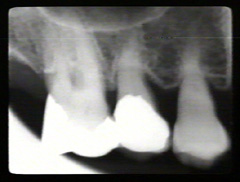

Estas

imagenes fueron producidas por Rolf Attstrom y la Asociación Dental

Dinamarquesa en colaboración con Video Goof, Dinamarca. Cámara y videoediting Tommy Ols, Videocompiling y Grabación

Anders Nattestad